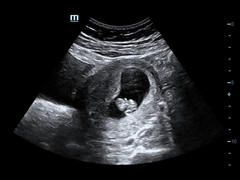

Had my private scan last night and baby is well, doing a headstand and measuring 8w5d today. So hard to get head around fact that's happening inside. Could see clear heart flicker, round head, arm and leg buds, and spine. Got some nice wee video clips too. Grin Time to try to chill out now!!